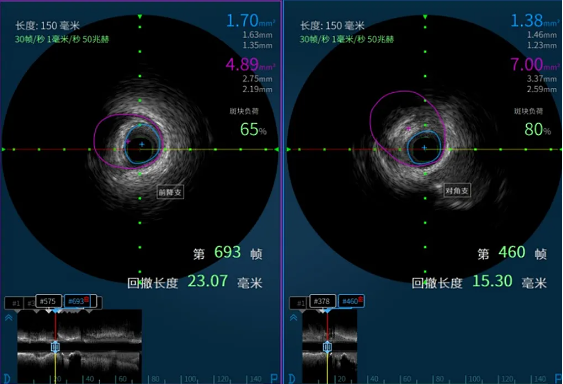

在医院心血管内科主任李昌教授的指导下,阳逻院区心内团队运用冠状动脉血管内超声(IVUS)技术详细检查患者血管,发现主支血管狭窄程度处于临界状态,可暂时通过药物治疗来优化;分支血管严重狭窄,需要进行介入治疗。基于IVUS提供的精准信息,患者避免了不必要的支架植入,有效降低手术风险。这一精准化治疗方案,既减少患者创伤与经济负担,又降低术后并发症风险,为患者的健康提供了有力保障。

患者IVUS检查影像报告